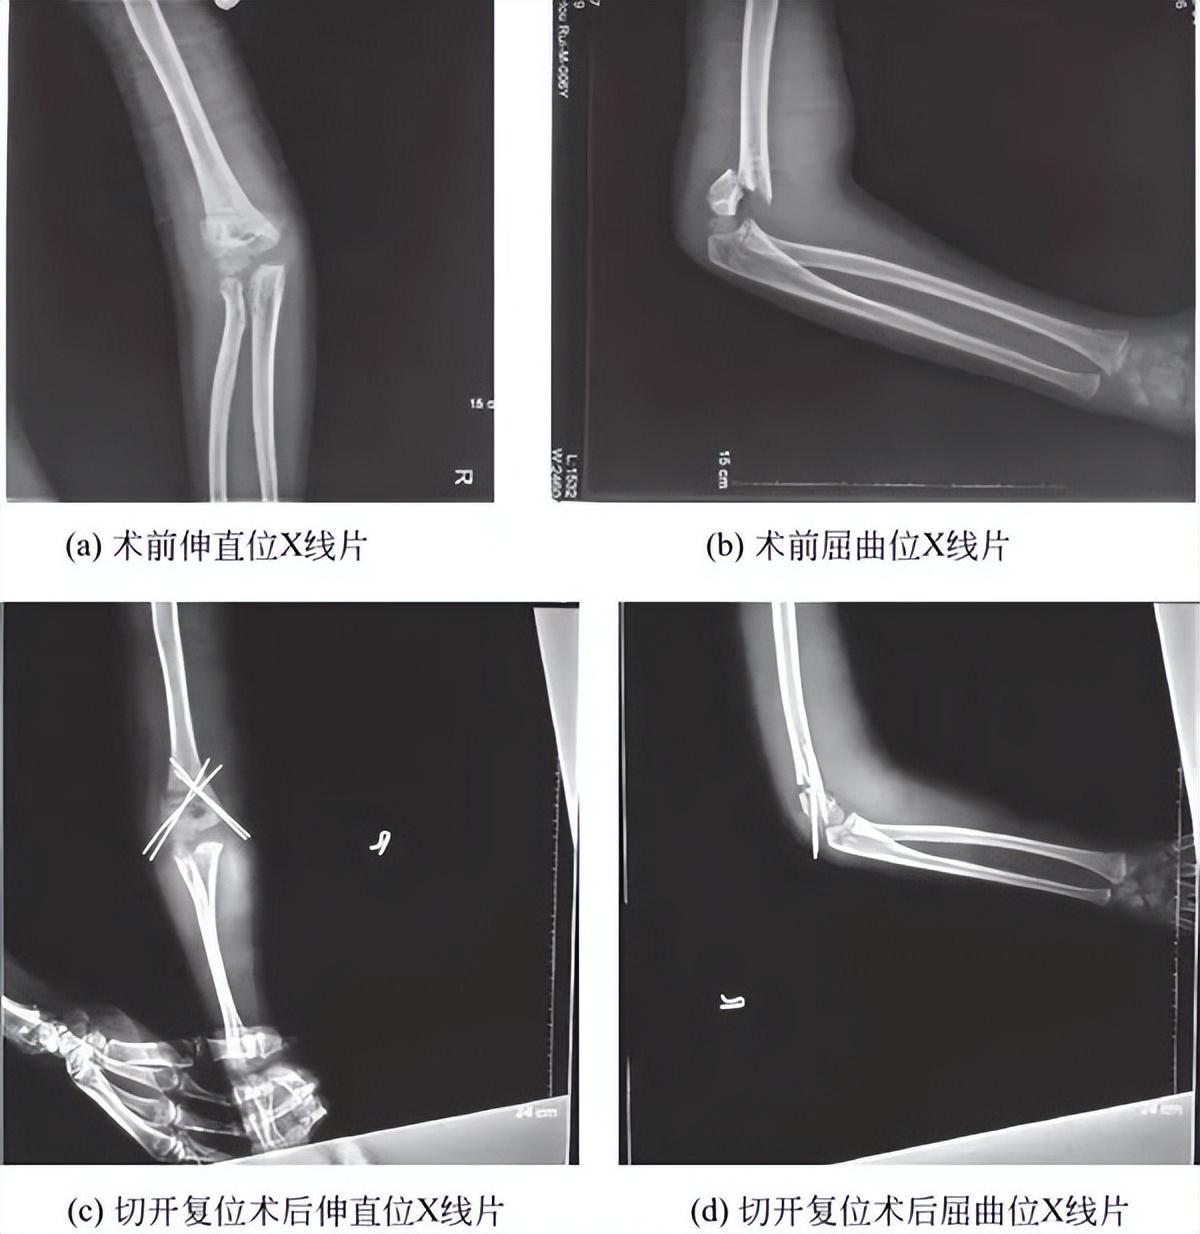

(3)Ⅲ型肱骨髁上骨折:所有的Ⅲ型肱骨髁上骨折复位经皮克氏针内固定是目前Ⅲ型髁上骨折的标准治疗方法。通常可闭合复位经皮克氏针内固定,但若软组织嵌入不能解剖复位或存在肱动脉损伤者需切开复位(图2)。

图2 肱骨髁上骨折术前术后X线片